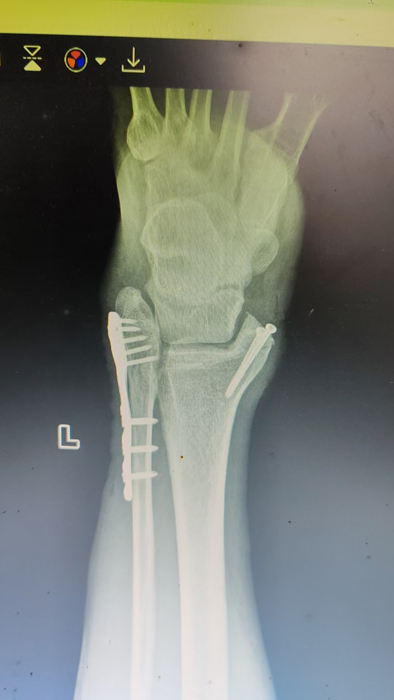

2月4日,何店镇中心卫生院接诊一名左踝关节外伤患者,经影像检查,确诊为左胫、腓骨下段骨折。外科医生姜稳迅速完成术前检查及病情评估,并与患者及家属深入沟通治疗方案。在患者强烈要求于本院进行手术的情况下,为最大限度保障手术质量与安全,该院特邀请医共体牵头单位——曾都区人民医院脊柱创伤外科专家团队前来指导。

本次帮扶由曾都区人民医院脊柱创伤神经外科主任徐三军带队,专家团队抵达后立即完成手术风险评估及术前准备。手术过程中,徐三军主任严格规范完成各项手术操作,并同步结合手术步骤,为该院外科医师详细讲解骨折手术的关键要点、操作技巧、术中注意事项及术后康复要领。通过“手把手”的实战带教,专家将丰富的手术经验与规范的诊疗思路倾囊相授,让该院医护人员在实操中学习,在过程中成长。